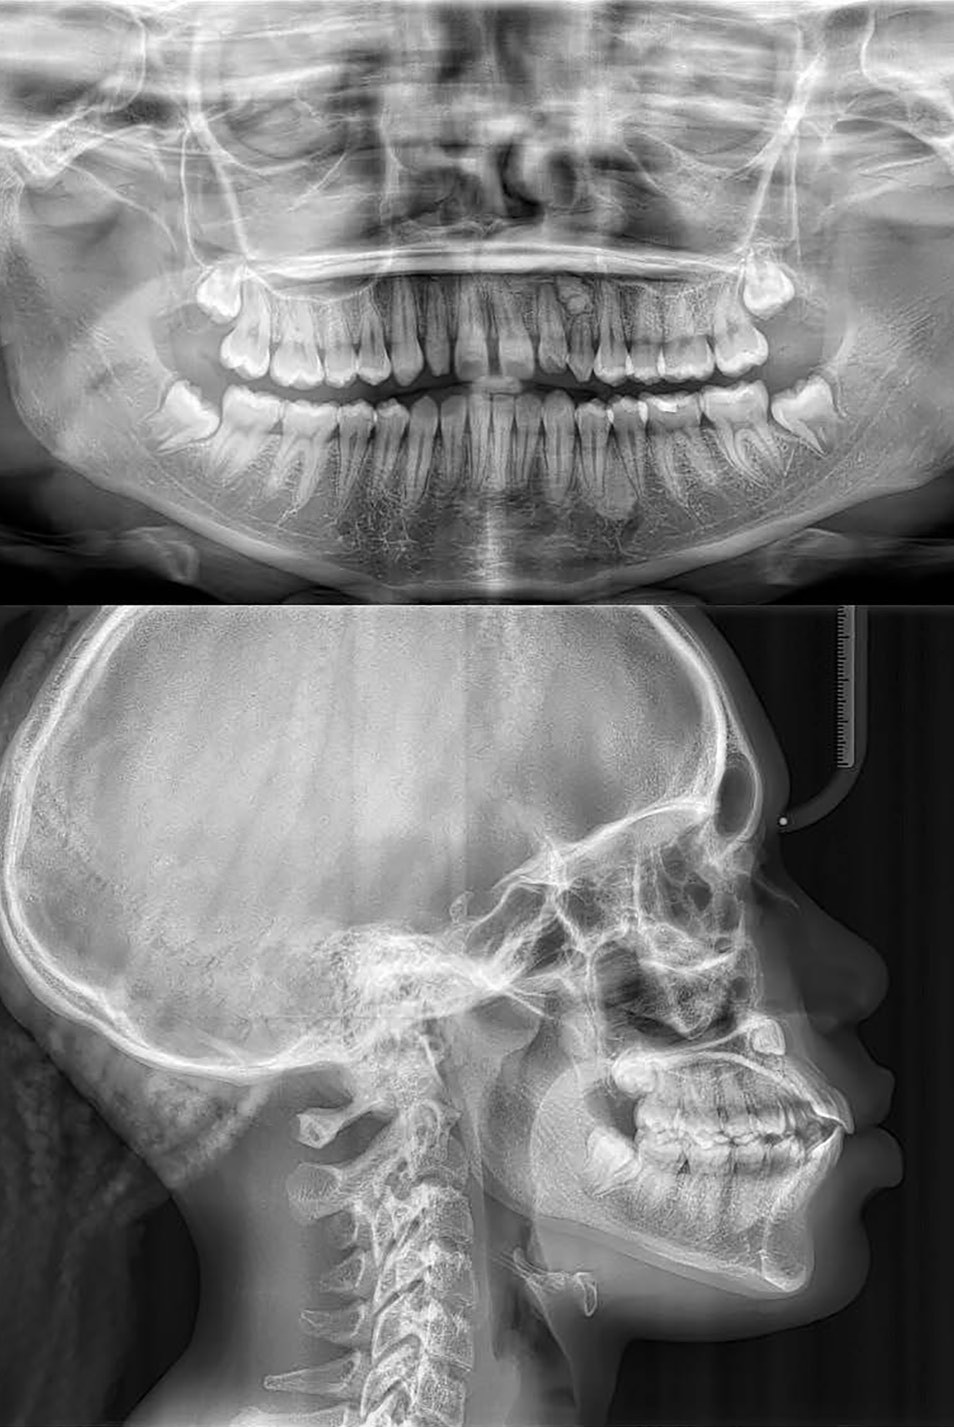

Diagnostic (fig. 1 et 2)

À l’examen extra-oral, la patiente présente un profil biprognathe associé à une Classe II squelettique modérée dans un contexte de normodivergence. L’angle naso-labial apparaît ouvert, le sillon labio-mentonnier est marqué et une prochéilie mandibulaire est observée. Le sourire se révèle disharmonieux, avec une faible visibilité des dents maxillaires.

À l’examen intra-oral, les arcades sont paraboliques, la courbe de Spee est normale. On remarque l’absence de la 23 sur l’arcade ainsi que la persistance de la 63. La patiente présente une Classe II partielle molaire et canine subdivision droite, ainsi qu’une insuffisance de recouvrement. Un léger encombrement incisif mandibulaire est présent, ainsi que des diastèmes maxillaires avec une dysmorphie dento-dentaire de 12 et 22.

L’examen fonctionnel révèle une ventilation nasale et une déglutition mature.

La radiographie panoramique permet de confirmer l’inclusion de la 23, apicale aux dents 21 et 22, ainsi que la présence d’un odontome en apical de la 63. Ces éléments nécessitent la réalisation d’un CBCT.

La téléradiographie de profil montre une Classe II squelettique par biprognathie, avec proalvéolie et vestibuloversion de l’incisive mandibulaire.